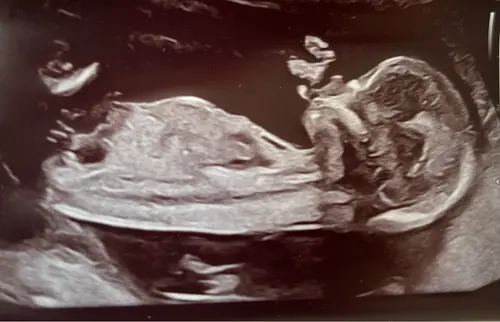

Ik zelf zie hem ook niet echt maar ook te weinig verstand van ik zal nog eens een andere erbij zetten van dezelfde echo

Oeh lastig, ik zie wel een nub maar vind het lastig om te zien of deze nu meer in een driehoek staat tov de ruggengraat of dat het recht door loopt 😅. Misschien zijn er kenners die het zien?